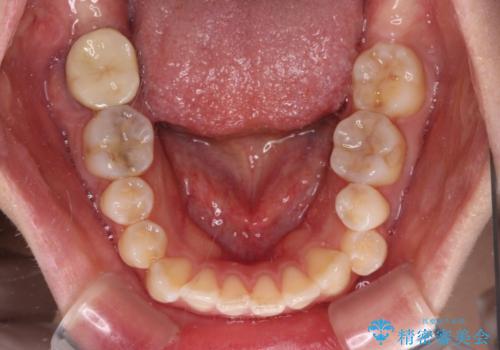

八重歯と開咬の抜歯矯正 ワイヤー装置を併用したインビザライン矯正治療

- 咬み合わない前歯と八重歯などのデコボコを気にして来院された患者様です。

上下前歯の位置を比較すると上顎が前方にあり、デコボコ改善でより上顎が前方に行く可能性があります。

開咬の改善にはインビザラインが有効であり、インビザライン単体での治療を検討しましたが、上顎前突を回避するために上顎左側第一小臼歯抜歯を行うこととしたため、補助装置とワイヤー矯正を併用した上で、インビザラインによる矯正治療を行うこととしました。

インビザライン矯正治療では、臼歯の圧下による前歯部の早期接触が大きな問題となっています。開咬では、その臼歯圧下を逆手にとって前歯部の非接触を改善させることができます。